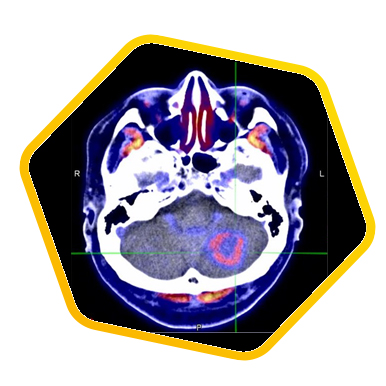

PET/CT Simulator for Radiotherapy Treatment Planning

PET/CT Simulation is a one-stop imaging facility for both metabolic evaluation and CT simulation in radiotherapy treatment planning. The efficacy of radiotherapy relies on maximizing radiation dose to tumor and preserving normal tissues. Click here for more details.